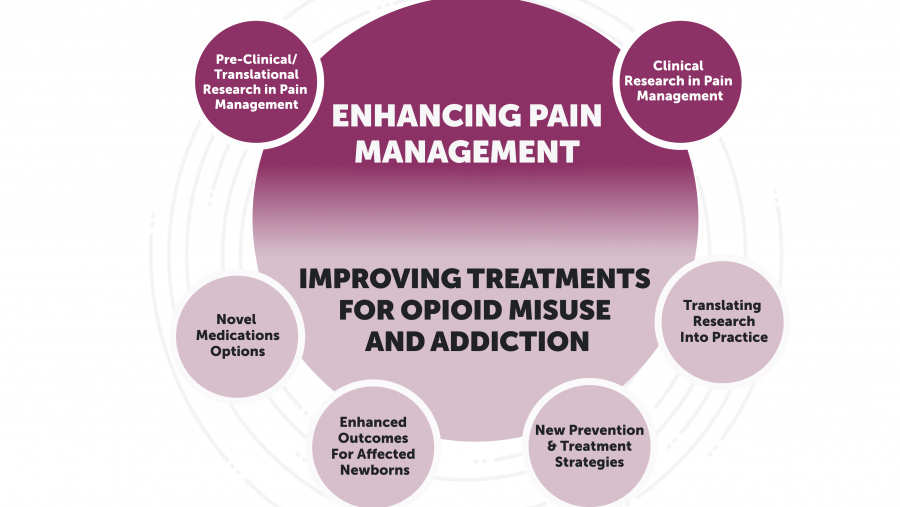

NIH researchers are exploring several promising directions and developments to better support people living with pain